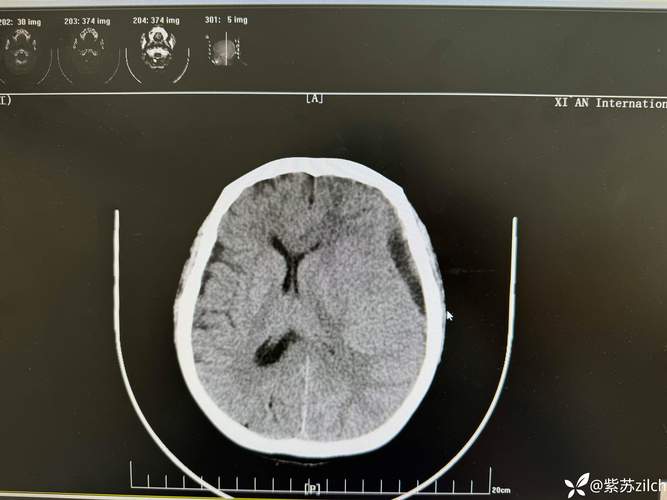

| 影像学检查 (CT/MRI) | CT上表现为高密度(白色)阴影,非常清晰 | CT早期可能正常,24-48小时后出现低密度(黑色)阴影。MRI对早期脑梗更敏感 |